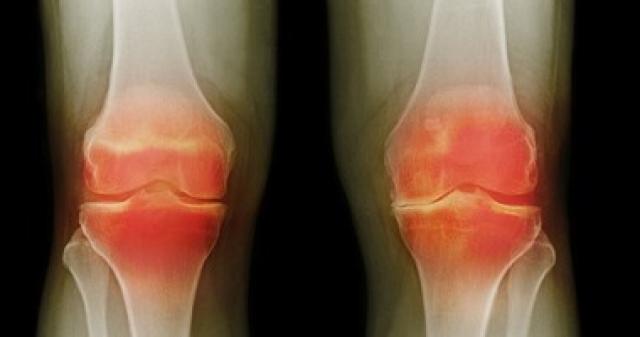

في اليوم العالمي لالتهاب المفاصل.. لماذا يصيب النساء أكثر من الرجال؟

وحسبما ذكر موقع "intermountain healthcare"، فإن النساء تصاب بالتهاب المفاصل أكثر من الرجال، بسبب أن لديهن مرونة أكثر في الأوتار، ولذلك يؤثر الالتهاب على مفاصل الفخذ عند الرجل، بينما يؤثر على مفاصل اليدين والركبة والفخذين عند النساء.

وتعد زيادة الوزن وسيلة للإصابة بالتهاب المفاصل أيضًا، ولأن السمنة أكثر شيوعًا بين النساء عن الرجال، فإن ذلك يضغط على مفاصل الركبة ويؤدي إلى تآكل الغضاريف مع التقدم في السن، وبالتالي تحدث الإصابة بالتهاب المفاصل.